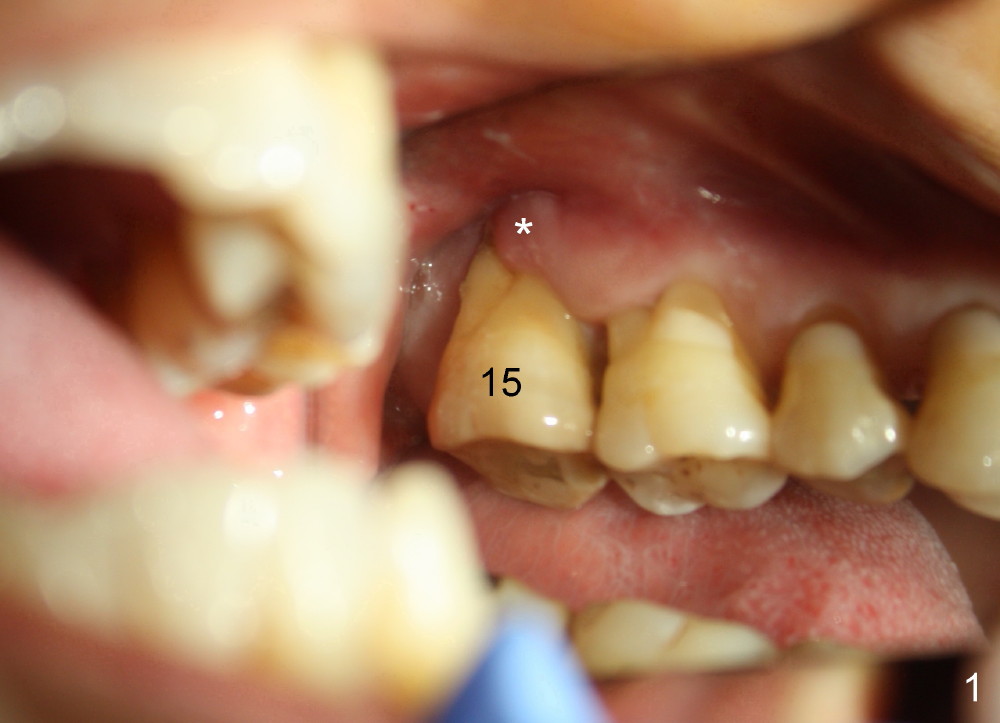

Gingival Recession

A 56-year-old female has recurrent infection and buccal gingival recession (Fig.1 *) after root canal therapy in the upper left 2nd molar (Fig.2). The extraction socket is single and large. Osteotomy forms by using a series of osteotomes (2-5 mm in diameter) mesiopalatal to the center of the socket. The sinus floor is thin (approximately 2-3 mm). The osteotomy is further enlarged by inserting 4.5-8 mm taps at the depth between 14 and 17 mm from the gingival margin. The last tap has barely achieved stability (Fig.3). It appears that the tap has almost obliterated the socket. Allograft is pushed into the sinus before placement of a 8x17 mm implant. The insertion torque is between 15 and 20 Ncm (Fig.4). The gingiva-level implant is slightly subgingival except buccal (Fig.5). To facilitate buccal gingival re-growth and cover the exposed implant surface, bone graft is placed subgingival (Fig.5 ^). The gingival sulcus is closed partially by placement of a thin strip of collagen membrane (not shown). The wound is protected by applying perio dressing.

Next time she returns 4.5 months postop, bone looks normal around the implant (Fig.7), whereas the buccal gingival recession appears to get worse with 1-2 implant thread exposure (Fig.8 >). To avoid this complication, the initial osteotomy should be placed as palatal as possible; when the implant is placed with gingival recession (Fig.5), soft tissue graft should be performed. The implant should be smaller.